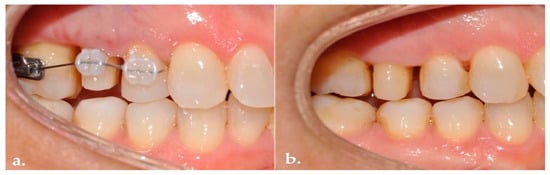

Background: Subcrestally placed implants (SPIs) present advantages for bone preservation and soft tissue support but pose challenges in maintaining peri-implant soft tissue health. This case explores the role of Crest to Restoration Distance (CRD) in the development and resolution of peri-implant mucositis. Case [...] Read more.

Background: Subcrestally placed implants (SPIs) present advantages for bone preservation and soft tissue support but pose challenges in maintaining peri-implant soft tissue health. This case explores the role of Crest to Restoration Distance (CRD) in the development and resolution of peri-implant mucositis. Case Presentation: A 57-year-old woman received two SPIs—one in the upper left and one in the lower right first molar region. Despite similar implant systems and prosthetic protocols, the upper left implant developed mucositis, characterized by bleeding on probing and discomfort, while the lower right implant remained stable. Three-dimensional analysis using cone-beam computed tomography (CBCT) revealed excessive CRD at the affected site. Results: After prosthodontic revision to reduce the CRD, clinical signs of mucositis resolved, with probing depths reduced to less than 1 mm and no bleeding on probing. The control site remained healthy throughout the observation period. Practical Implications: This case highlights CRD as a modifiable prosthetic factor influencing soft tissue stability. A three-zone model—comprising the sulcus, transitional zone (TZ), and subcrestal zone (SZ)—is introduced to provide a biologically grounded framework for understanding soft tissue adaptation around SPIs. Full article

Figure 1